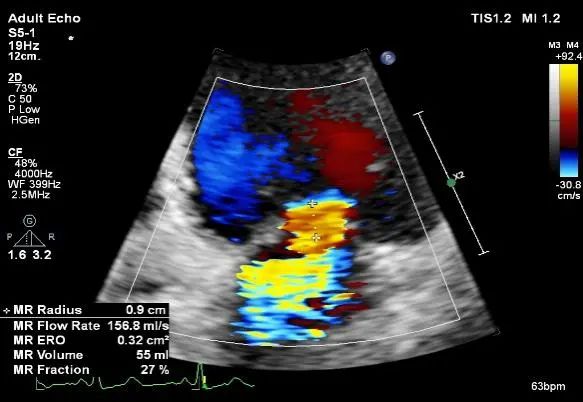

术前TTE

最大返流面积20.9cm²,LA:53mm

ERO:0.95cm²,Rvol:108ml,RF:51%,VC:9.3mm